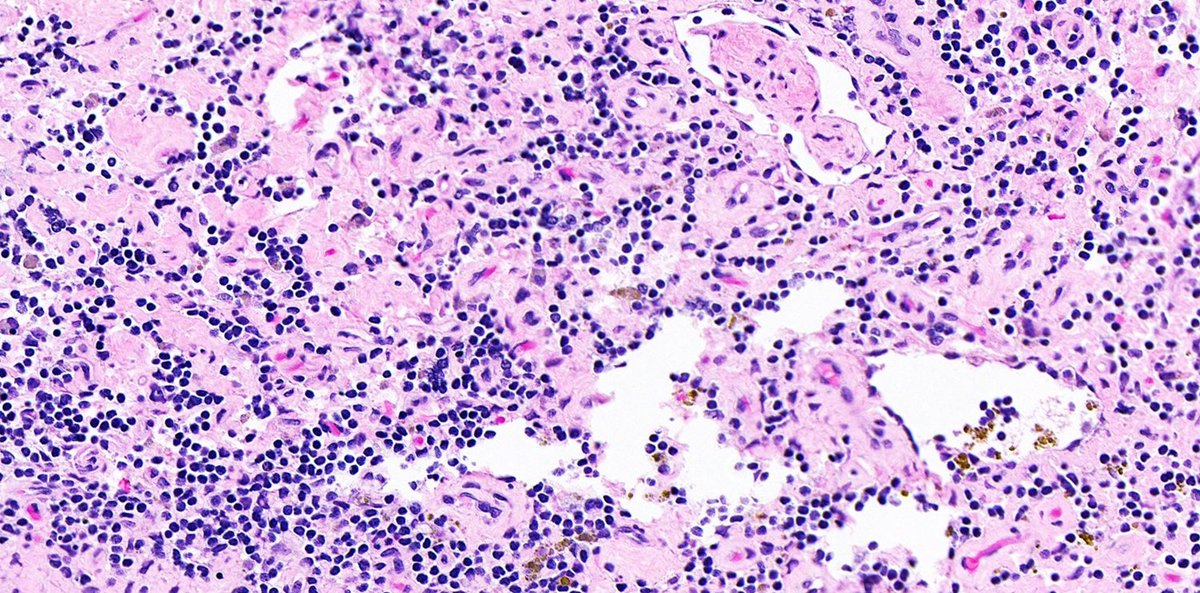

Lung biopsy illustrating a spectrum of involvement by lymphomatoid granulomatosis➡️ 🩸Grade 1: Polymorphous angicentric lymphoid infiltrate without significant atypia; necrosis is absent. Large EBV-positive lymphoid cells are rare. #hemepath #lymsm #thoracicpath #PathTwitter